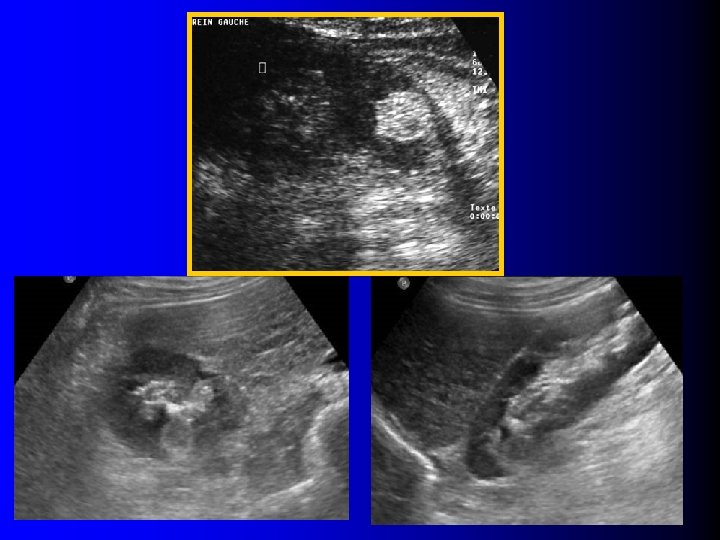

Echographie l Tumeur rénale: – Hyperéchogène (>90%) – Homogène (>90%) – Atténuante (30%)

Echographie l Tumeur rénale: – Hyperéchogène (>90%) – Homogène (>90%) – Atténuante (30%)